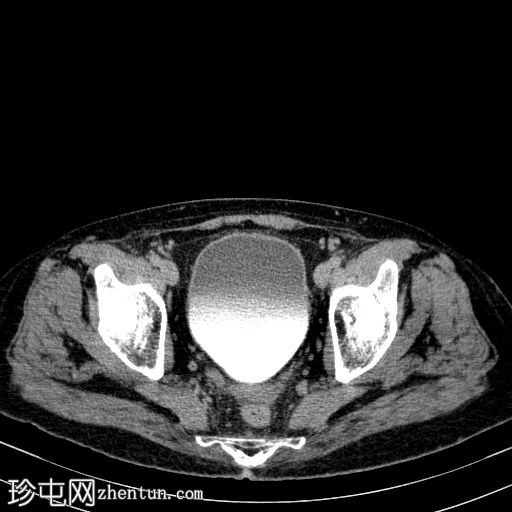

轴向C+门静脉期

8.jpg

胰体尾弥漫性增大,特征为胰腺实质低强化,无明显坏死区域。

该病灶与以下表现相关:

胰周筋膜平面边界不清的污迹,无明显壁形成、气室、固体碎片或血液产物。

病变横向延伸至左前肾旁间隙,伴有Gerota筋膜增厚。

病变向下延伸至盆腔。

无肠系膜或脾脏血管阻塞的证据。

未见导管扩张或钙化。